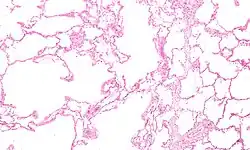

COPD develops as a significant and chronic inflammatory response to inhaled irritants which ultimately leads to bronchial and alveolar remodelling in the lung known as small airways disease.[93][94][95] Thus, airway remodelling with narrowing of peripheral airway and emphysema are responsible for the alteration of lung function.[55] Mucociliary clearance is particularly altered with a dysregulation of cilia and mucus production.[96] Small airway disease sometimes called chronic bronchiolitis, appears to be the precursor for the development of emphysema.[97] The inflammatory cells involved include neutrophils and macrophages, two types of white blood cells. Those who smoke additionally have cytotoxic T cell involvement, and some people with COPD have eosinophil involvement similar to that in asthma. Part of this cell response is brought on by inflammatory mediators such as chemotactic factors. Other processes involved with lung damage include oxidative stress produced by high concentrations of free radicals in tobacco smoke and released by inflammatory cells and breakdown of the connective tissue of the lungs by proteases (particularly elastase) that are insufficiently inhibited by protease inhibitors. The destruction of the connective tissue of the lungs leads to emphysema, which then contributes to the poor airflow and finally, poor absorption and release of respiratory gases. General muscle wasting that often occurs in COPD may be partly due to inflammatory mediators released by the lungs into the blood.[14]

Emphysema is defined as enlarged airspaces (alveoli) whose walls have broken down, resulting in permanent damage to the lung tissue. Chronic bronchitis is defined as a productive cough that is present for at least three months each year for two years. Both of these conditions can exist without airflow limitations when they are not classed as COPD. Emphysema is just one of the structural abnormalities that can limit airflow and can exist without airflow limitation in a significant number of people.[12][13] Chronic bronchitis does not always result in airflow limitation. However, in young adults with chronic bronchitis who smoke, the risk of developing COPD is high.[14] Many definitions of COPD in the past included emphysema and chronic bronchitis, but these have never been included in GOLD report definitions.[9] Emphysema and chronic bronchitis remain the predominant phenotypes of COPD, but there is often overlap between them, and several other phenotypes have also been described.[11][15] COPD and asthma may coexist and converge in some individuals.[16] COPD is associated with low-grade systemic inflammation.[17]

Many definitions of COPD in the past have included chronic bronchitis and emphysema, but these have never been included in GOLD report definitions.[9] Emphysema is defined as enlarged airspaces (alveoli) whose walls break down resulting in permanent damage to the lung tissue and is just one of the structural abnormalities that can limit airflow. The condition can exist without airflow limitation, but commonly it does.[12] Chronic bronchitis is defined as a productive cough that is present for at least three months each year for two years, but does not always result in airflow limitation, although the risk of developing COPD is great.[14] These older definitions grouped the two types as type A and type B. Type A were emphysema types known as pink puffers due to their pink complexion, fast breathing rate and pursed lips. Type B were chronic bronchitic types referred to as blue bloaters due to low oxygen levels causing a bluish color to the skin and lips and swollen ankles.[48] These differences were suggested to be due to the presence or not of collateral ventilation, evident in emphysema and lacking in chronic bronchitis.[49] This terminology was no longer accepted as useful, as most people with COPD have a combination of both emphysema and airway disease.[48] These are now recognized as the two major phenotypes of COPD — the emphysematous phenotype and the chronic bronchitic phenotype.[11]